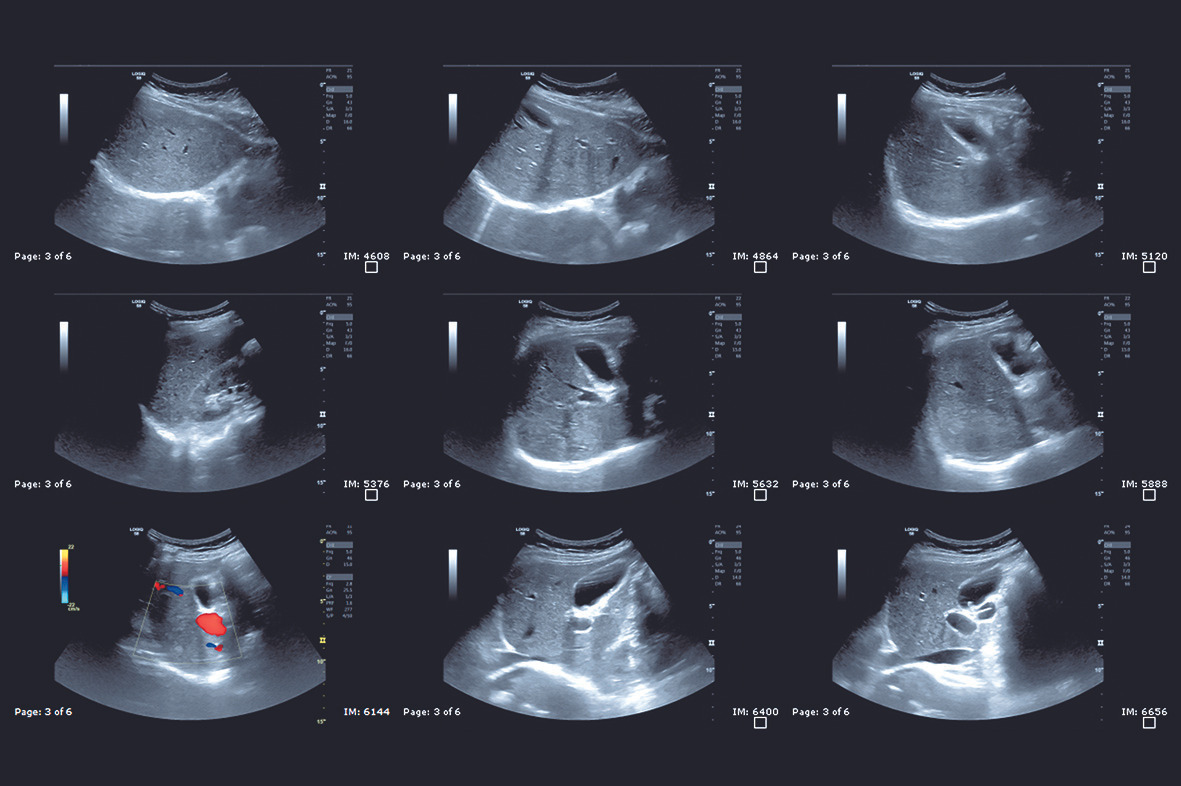

복부 초음파는 고주파 음파를 이용하여 인체 내부의 구조를 영상으로 재현하는 검사입니다. 초음파 기기가 발생시키는 음파가 인체 조직에 반사되어 돌아오는 신호를 분석하여 화면에 실시간으로 영상을 띄우게 됩니다. 이 과정에서 인체의 장기 구조뿐 아니라 혈류의 흐름, 혹은 병변의 위치와 크기 등을 정확하게 파악할 수 있습니다.

또한, 복부 초음파 검사는 의료진에게 환자의 전반적인 복부 건강 상태를 빠르게 파악할 수 있는 정보를 제공하여, 환자 맞춤형 치료 및 관리 계획 수립에 큰 기여를 합니다. 최근에는 초음파 기술의 발전으로 인해 영상의 해상도와 정확도가 크게 향상되었으며, 이를 통해 더욱 섬세한 진단이 가능해졌습니다.